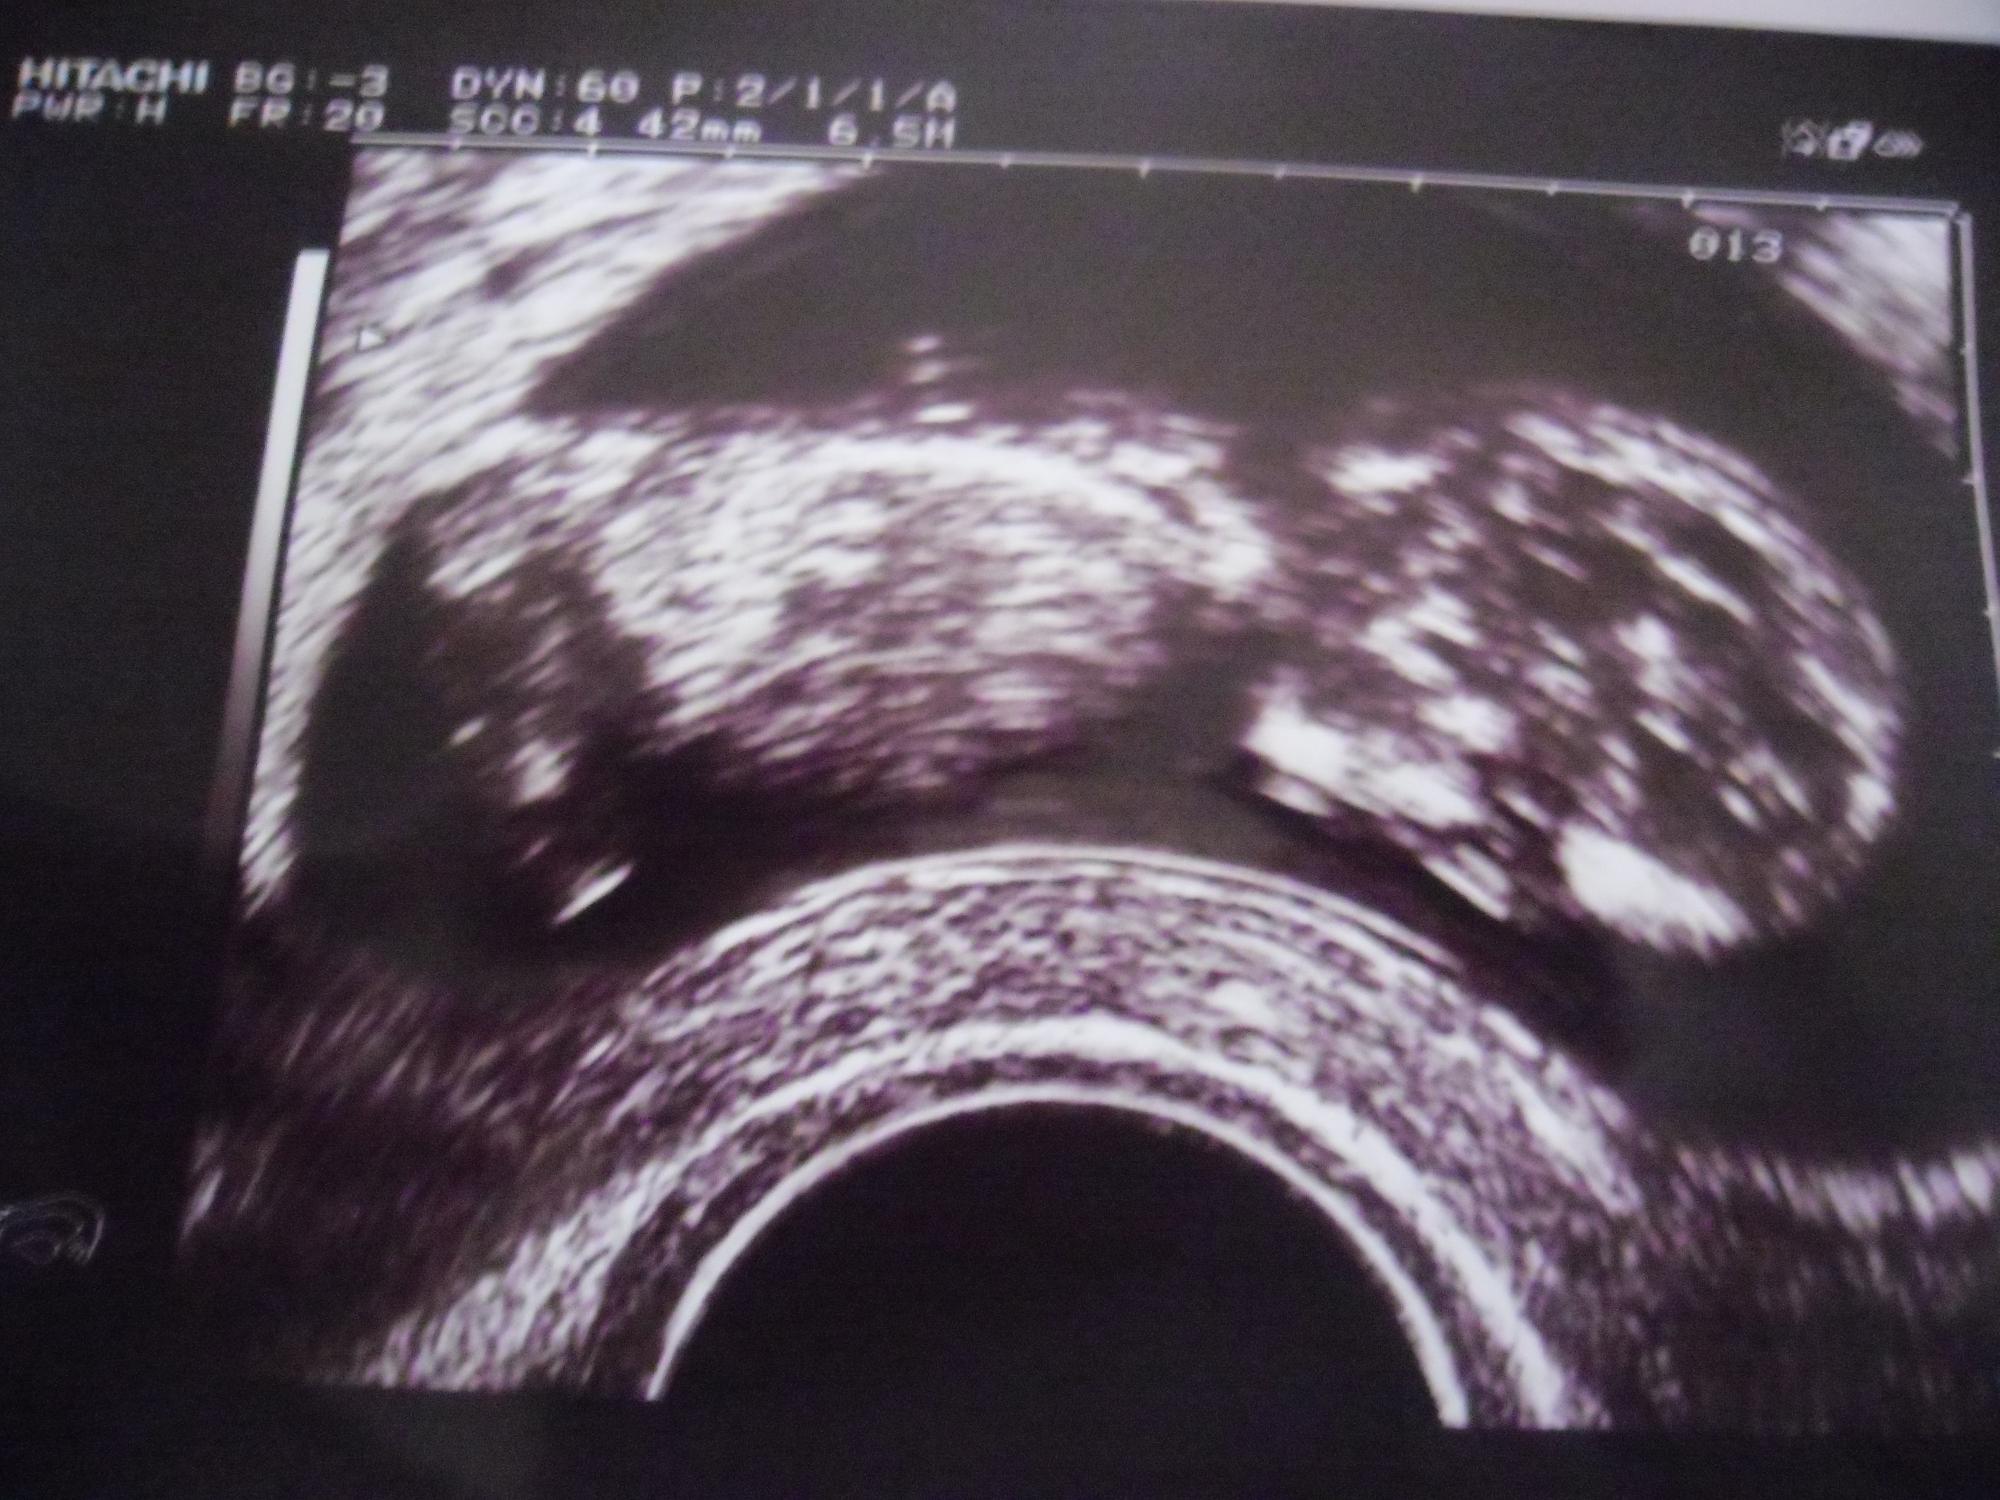

@me: war heute beim ultraschall. alles ist gut. Baby ist 5cm groß und alles sieht normal aus. Nfm hab ich aber nicht machen lassen.

Dateianhänge

kl.jpg

ilo: tolle bild. freut mich das alles gut ist. :dance: :dance: :dance: :dance:

Ilo86: Schönes Bild. Super, das alles in Ordnung ist!! *dd* *dd*